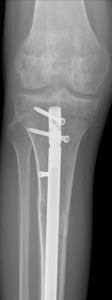

Nonunion and malunion repair related to post-traumatic conditions and/or prior surgery

Acute fracture care of the pelvis and the extremities